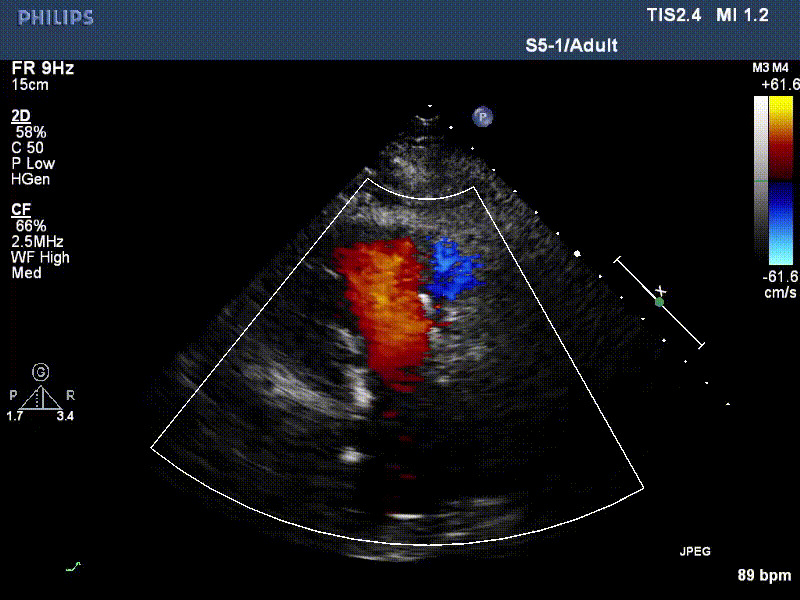

流并分別伴有房顫和房撲,高外科手術(shù)風(fēng)險(xiǎn)。術(shù)前超聲提示,兩例患者下腔靜脈寬度分別為13mm和29mm,右房?jī)?nèi)徑(上下徑和左右徑)分別為52×41mm和53×43mm,彩色多普勒顯示極重度三尖瓣反流,VCW分別為14×15mm和10mm。

1年前,兩例患者因難治性雙下肢水腫輾轉(zhuǎn)多家醫(yī)院尋求救治,考慮到兩例患者高齡、基礎(chǔ)疾病多、STS評(píng)分高,不適合傳統(tǒng)外科開(kāi)胸手術(shù),葛均波院士及其團(tuán)隊(duì)周達(dá)新教授、潘文志教授、張?jiān)床┦俊㈥惿┦俊㈥惖さげ┦?/strong>聯(lián)合心外科王春生、魏來(lái)主任,麻醉科繆長(zhǎng)虹、郭克芳主任以及心超室的潘翠珍教授、李偉教授共同討論決定,采用我國(guó)創(chuàng)新器械LuX-Valve Plus經(jīng)血管三尖瓣置換系統(tǒng)為患者進(jìn)行手術(shù)。相較于第一代產(chǎn)品LuX-Valve,LuX-Valve Plus經(jīng)血管三尖瓣置換系統(tǒng)對(duì)輸送系統(tǒng)進(jìn)行了全面升級(jí),實(shí)現(xiàn)了經(jīng)頸靜脈入路的方式,進(jìn)一步減小了手術(shù)風(fēng)險(xiǎn)和對(duì)患者的創(chuàng)傷。目前隨訪(fǎng)1年心超結(jié)果顯示,三尖瓣極重度反流消失,人工三尖瓣瓣膜穩(wěn)定牢固,瓣葉活動(dòng)度良好,右心室及下腔靜脈明顯縮小,心輸出量增加。兩位老人手術(shù)后沒(méi)有出現(xiàn)過(guò)胸悶氣促的癥狀,下肢水腫緩解,活動(dòng)耐力提升,生活質(zhì)量也大為提高。

圖2 患者植入LuX-Valve Plus后,1年隨訪(fǎng)心超提示無(wú)三尖瓣反流